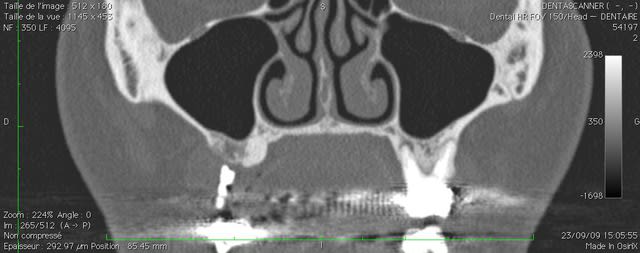

oui ça fait un gros prélèvement, c'est pour un cas particulier ou je dois virer 24, 25 et 26 avec de grosses lésions apicales et latérales, ou je voudrais conserver le maximum de volume osseux pour pouvoir implanter dans de bonnes conditions.

ci joint la pano et les coupes scan.